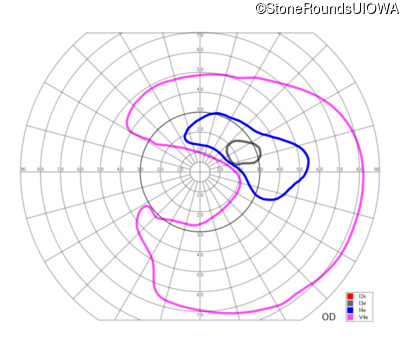

This 81 year old man began using a flashlight to read menus in his 40's. At age 75 his ophthalmologist noticed abnormal fundus findings and referred him to a retina specialist.

| Late Onset Retinal Dystrophy | C1QTNF5 | Ser163Arg AGC>AGA | AD |